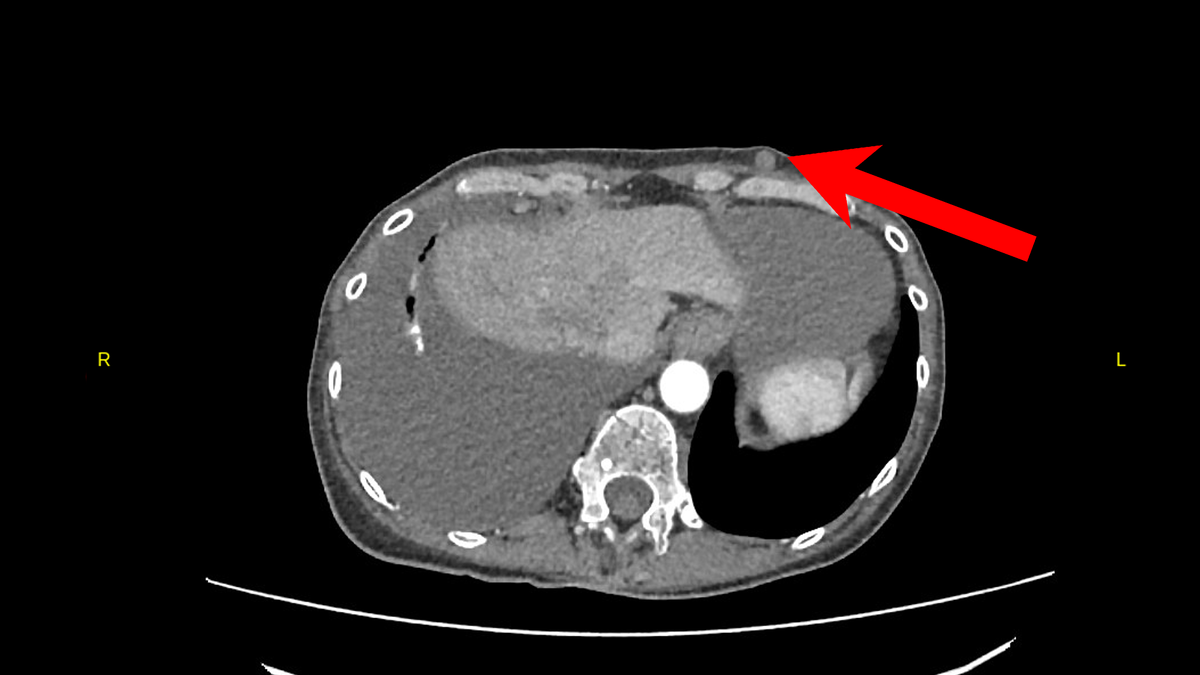

На приеме у онколога при тщательном осмотре были обнаружены несколько образований в мягких тканях, которые располагались в подкожно-жировой клетчатке туловища - на спине, животе, передней грудной стенке. Прикрепляю снимки КТ для иллюстрации.

Новообразованиие в мягких тканях туловища